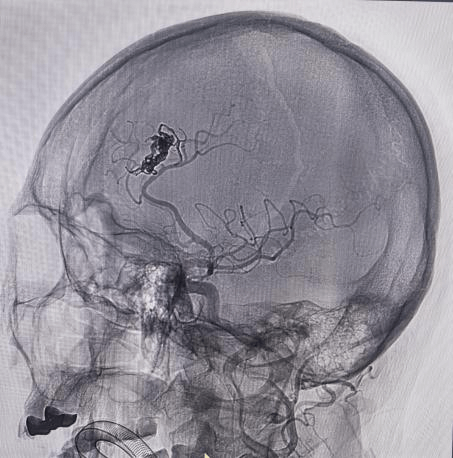

面对大动脉瘤且血管条件差的患者(腹主动脉S型迂曲,右侧颈总动脉II型牛角弓),以及颈内动脉多发动脉瘤的不同患者(C5-C7有5枚动脉瘤),吴全主任团队运用密网支架对症治疗,用一个支架巧妙解决大动脉瘤或多个动脉瘤难题,效果良好,患者短时间内快速恢复。

对于非责任动脉瘤的处理,医生们更是展现出专业与耐心。9个月前,患者动脉瘤破裂出血,当时造影发现2处动脉瘤,术中优先处理责任动脉瘤,待患者身体恢复后择期处理非责任动脉瘤。此次处理非责任动脉瘤,手术中造影,发现责任动脉瘤栓塞术后复发(3月前复查尚无),医生们当机立断,同期处理两个动脉瘤,省钱的同时,也成功为患者解除隐患。